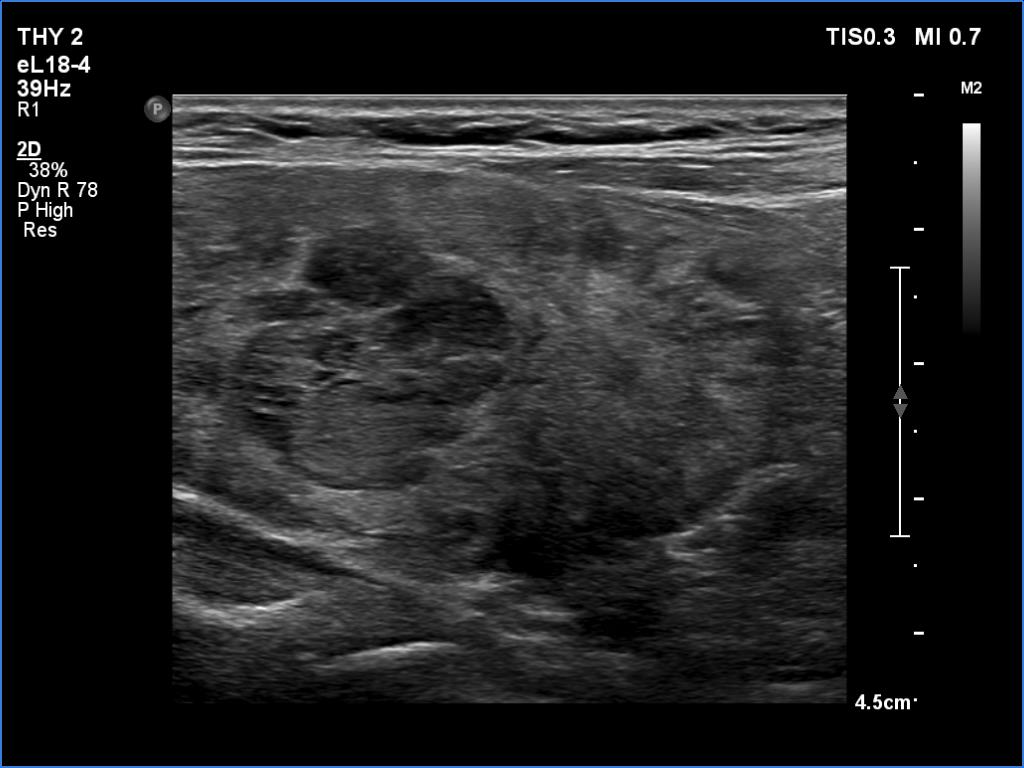

Comments.

- This case demonstrates the exception and not the rule. The echogenicity of a nodule almost always remains the same even over decades while in this patient the echogenicity has significantly changed two times within three years. The possible explanation is that the basic echo pattern of the extranodular thyroid and the vascularization influenced the pattern of the lesion.

- It is not evident whether the lesion in the right lobe is a single nodule with lobulated margins or a mass composed of multiple discrete lesions. In the former case the lobulation is pathological in the latter the undulation is not.